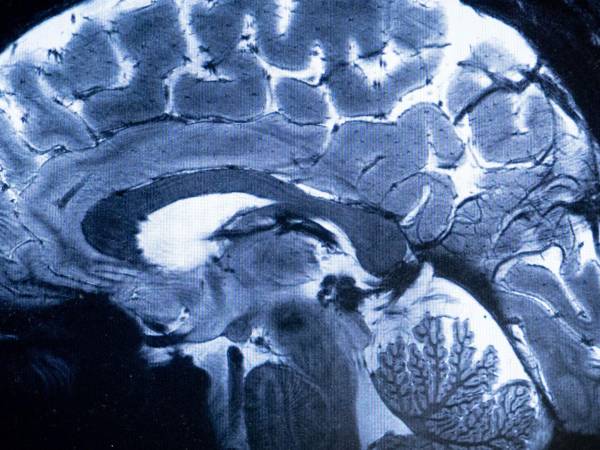

Hacer actividades aeróbicas por un mínimo de 30 minutos diarios y tratar de mantenerse en constante aprendizaje contribuye a la salud del cerebro.

¿Cómo se puede evitar la demencia y otras enfermedades del cerebro?

Una mala salud cerebral puede provocar demencias, epilepsias, hemorragias y hasta infartos cerebrovasculares. Los siguientes hábitos ayudan a prevenir esos problemas